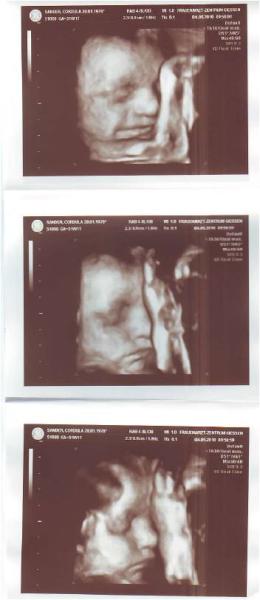

Ich komme grad von der VU :-) War heute ganze 2 Stunden in der Praxis - die Sprechstundenhilfe fragte schon ob sie mir ein Feldbett für heute Nacht besorgen soll :-))) Erst "normale" Vorsorge beim Doc. Alles prima. Muttermund zu und 4cm, Maße alle im Normbereich. FL=6,2 - sprich müssten dann ca. 43cm entsprechen Gewicht 2000g Dann kam CTG dran... auch alles prima... keine Wehen, Herzschlag super. Sie hat allerdings ständig versucht die beiden CTG Messdingsbums weg zu strampeln *hihi* Und zur Krönung dann noch ein letztes Mal 4D Ultraschall. Hach war das wieder cool. Er hat das jetzt 3mal gemacht und jetzt hab ich auch endlich die DVD von allen 3mal.... ist das spannend da nochmal zu zuschauen. Toxo machen sie jetzt noch das 3. Mal und Hepatitis wird geprüft. Hach so langsam bin ich gespannt wie ein Flitzebogen auf die kleine Zicke :-)

Ich denke auch ständig sie ist viel größer als "normal" für diese Woche aber mein Doc meinte es wäre alles im grünen Bereich.... Na hauptsache es geht ihr gut ;-) Hab hier mal ein paar Fotos von heute eingescannt :-)

Na die ist ja zuckersüß!!! Hat schon ordentlich Bäckchen!!! Zum Knuddeln!!!